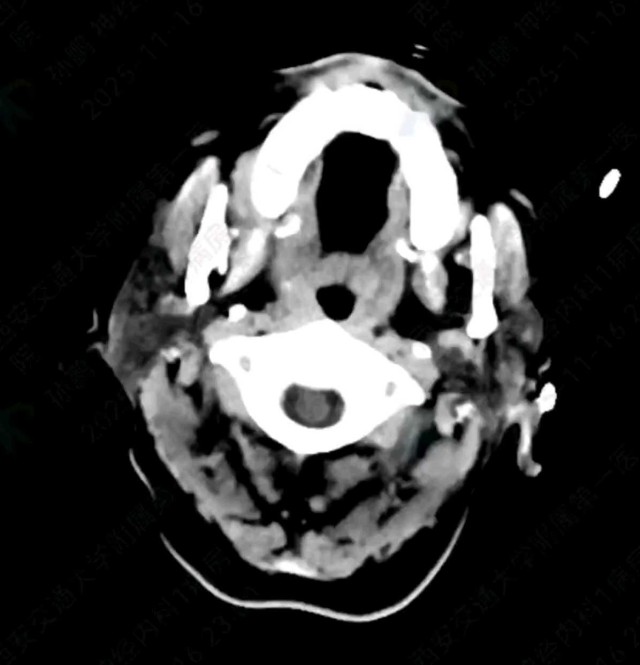

灼见|如果是你,如何处置山东男孩(多器官切除病例)

文/西地兰 特别声明:所有观点仅代表个人言论 特别声明:与当事双方均无利益相关 山东男孩,目前全网沸沸扬扬,看过一些观点,直言不讳地说,大多偏颇。要么一股脑地指责医方的全责,甚至有说千万别在县医院看病。要么又为医方无休止的遮羞,认为这样的手术在县医院做下来已经非常了不起。而我想到的是,以后面临类似的病例,我们怎么办?那么我们不如来一次专业的病案讨论。既然是事后讨论,难免有事后诸葛亮的感觉,但是假如下一次,同行们遭遇这样的病例,如何处置?这是医疗行业所面临的问题。希望我整理的这些思路和相关病例,对同行们有所帮助!就目前的资讯外界不足以判断是否需要急诊,如果需要急诊,那么只能根据术中所见进行处理,

目前知道的消息,第一,术前发现一个血肿,然后做增强CT发现一个占位,没说血肿与肿瘤的关系,术后病理没有描述肿瘤出现破裂出血,大概率就一个小血肿,我就不明白当地主任凭哪个指针去给这小孩开急诊刀的?哪个指南告诉他需要急诊开?第二,诊断不明确他想的不是进一步检查,一边观察一边进一步查,他反而选择腹腔镜探查,这个探查的指针在哪?第三,腹腔一个血肿,没有活动性出血,没有血压心率出现问题,为什么要开腹进去碰它?不能等血肿吸收再明确肿瘤性质吗?第四,1点进腹,3点病理结果出来,按这个时间还算顺利,应该还没出事,孩子还算平稳,病理是低度恶性,切了就治愈,他一年能开几台这手术,就敢继续做,拿孩子练手。第五,后面